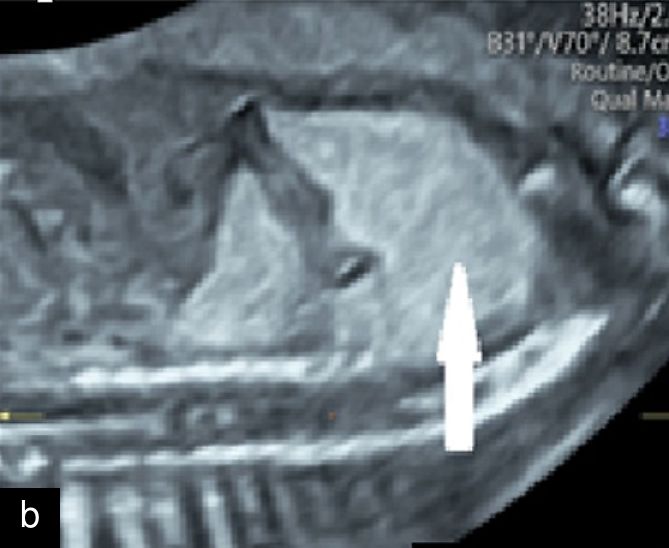

11

Axial (a) and sagittal (b) views of congenital pulmonary airway malformation (arrow) in the left lung with mediastinal shift at 20 weeks.